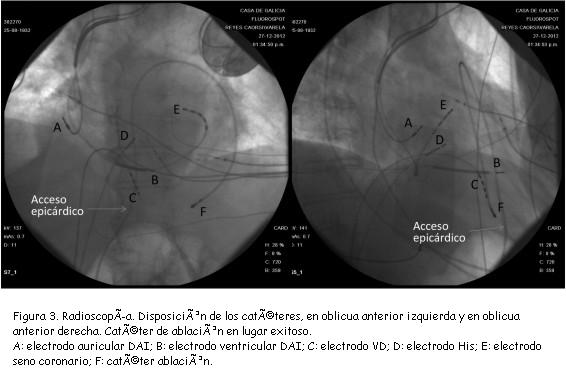

El paciente ingresa a sala en TVSM de 105 lpm bien tolerada hemodinámicamente (figura 1). No disponemos de ECG en ritmo sinusal previo. Dadas las características electrocardiográficas de la taquicardia, presencia de seudodelta, RS en precordiales con duración mayor a 121 ms desde inicio QRS a nadir de S, lo que podría sugerir su origen epicárdico, se decide establecer una estrategia que permita abordar epicardio y endocardio en un mismo procedimiento de ser necesario. Previamente a anticoagular al paciente con heparina sódica se realizó punción subxifoidea dejando guía en espacio pericárdico. Por acceso arterial femoral en forma aortica retrógrada se introduce en ventrículo izquierdo catéter con electrodo distal de 3,5 mm e irrigación externa para mapeo y ablación endocárdica. Utilizando sistema de navegación no fluroscópico EnSite-NavX® (St. Jude Medical, St. Paul, MN, USA), se realiza reconstrucción electroanatómica tridimensional del ventrículo izquierdo, y mapa de activación y de voltaje durante TVSM. Se topografía sitio de origen en sector en ínfero-latero-basal del ventrículo izquierdo; en ese lugar se consigue encarrilamiento con fusión oculta, precocidades de hasta 20 ms y potenciales medio-diastólicos, pero la aplicación de RF en ese sitio no interrumpe la taquicardia. Considerando las características del ECG y el fracaso de la ablación endocárdica se coloca introductor 8F en pericardio utilizando la guía previamente posicionada en dicho espacio. Se realiza cartografía de activación a nivel epicárdico con catéter 4 mm y el apoyo del sistema de navegación (figuras 2 y 3), consiguiendo en dicha zona (enfrentada a la endocárdica), precocidades de 88 ms además de potenciales meso-diastólicos (figura 4). Se aplica radiofrecuencia consiguiendo interrumpir la arritmia, que tampoco puede reinducirse. A las 48 horas reaparece la misma TVSM. Se repite procedimiento, no siendo posible el abordaje epicárdico en esta oportunidad por adherencias. Se interrumpe la arritmia con sobreestimulación y se intenta nuevamente control farmacológico. Este no es efectivo, reapareciendo la TVSM a las 72 horas; trasladado a sala de electrofisiología nuevamente, en esta ocasión se logra el acceso epicárdico, realizándose nuevo mapeo y ablación que logra interrumpir exitosamente la arritmia.